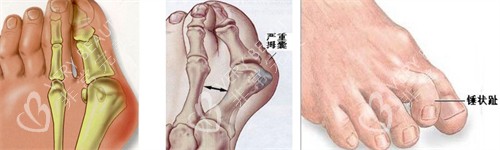

"您这属于复合型拇外翻,伴随前足弓塌陷。"马桂文医生拿着我的3D足部扫描图讲解时,我盯着墙上"26年专注足踝矫正"的锦旗直发怵。他笑着递来光导可视设备的屏幕:"看,这是您增生的骨赘,我们用5D微孔弧技术,通过3毫米的切口就能更准一些祛除。"

手术当天,我躺在特制的足部手术床上,看着医生用比圆珠笔还细的微型骨刀,在右脚内侧划出两道1厘米长的切口。"现在要调整跖骨角度了。"随着光导设备的嗡鸣,我能清晰看到屏幕上移位的骨头被"推"回原位,全程没碰钢钉,连止血都是用的生物胶。

"为什么能做到当天走路?"复查时我追着马桂文医生问。他调出我的手术视频:"传统手术要截断跖骨,用钢钉固定后需要2-3个月愈合。我们的5D微孔弧技术采用'弧面截骨'设计,配合光导复位器械,既保留骨骼完整性,又通过生物力学调整让足部自然承重。"